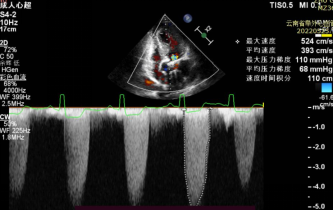

患者71岁老年女性,体重42kg,身高156cm,因突发活动后心累气紧合并心绞痛急诊入院,超声提示主动脉瓣膜重度狭窄,左心功能减低EF 46%,主动脉瓣峰值流速5.2m/s, 平均跨瓣压差68mmHg(图1),冠脉造影提示冠脉未见明显狭窄,患者合并COPD,TIA等并发症,STS评分>6分,经外科团队讨论提示传统外科高风险,经过多学科讨论拟行TAVR手术。术前CTA评价提示三叶式主动脉瓣(图2),Area 479.2mm²,Perimeter 77.9mm,Area折算瓣环直径24.7mm,左侧冠脉开口高度16.1mm,右侧冠脉开口高度16.5mm,瓣膜重度钙化,主要分布于瓣叶,LVOT无特殊,主动脉窦平均内径31mm,患者外周血管尚可无明显钙化扭曲,最细5.9mm(图3)。

停止起搏并撤回输送系统,撤出引导钢丝,关闭血管入路,术后造影及超声评价瓣膜功能良好,前向血流速度1m/s, 无明显瓣周漏(视频4)。

术后超声(视频4)